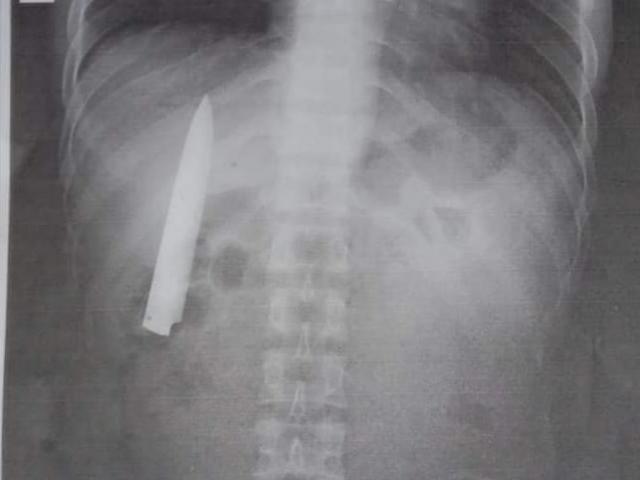

Sau khi ăn hết nửa đĩa măng lớn, Tiểu Ngô có triệu chứng đau bụng dữ dội vào ban đêm, đại tiện ra rất nhiều phân đen. Khi thấy vậy, gia đình vội vàng đưa anh đến bệnh viện cấp cứu. Bác sĩ nhận thấy bệnh nhân bị xuất huyết tá tràng rất nặng, máu không ngừng chảy ra.

Bác sĩ Lý Văn Giai, trưởng khoa Tiêu hoá, Bệnh viện Thường Châu II nói: “Bệnh nhân có một vết loét rất lớn ở tá tràng, những mạch máu lớn không ngừng chảy máu. Đây là dấu hiệu cực kỳ nguy hiểm”.